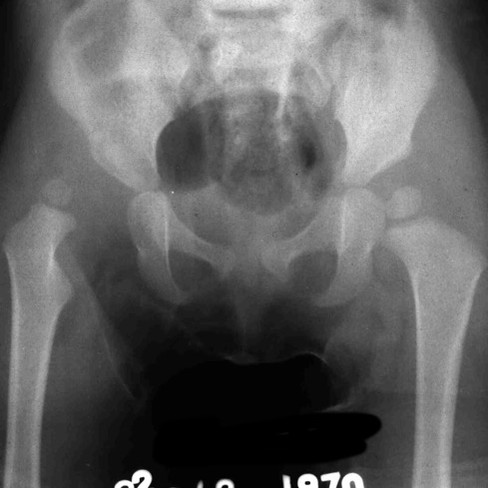

E successivamente mantenuta in divaricatore di Putti x diversi mesi. Come si può osservare dalla radiografia la testa del femore dx non solo è di ridotte dimensioni ma ha subito una crisi vascolare, come si vede dalla parte mancante. Questo fenomenoo denominato osteocondrite post-riduttiva è dovuto a una crisi vascolare dell’irrorazione della testa femorale

Alcuni mesi dopo, oltre ai disturbi della vascolarizzazione della testa femorale dx, si rende evidente un tetto inclinato o sfuggente. Di fronte al rischio di una perdita del risultato viene eseguita una tetto plastica. Si esegue una osteotomia del tetto che viene abbassato e reso orizzontale .

Il vuoto generato dalla correzione viene colmato con un cuneo di osso bovino. All’epoca non esisteva la banca dell'osso umano